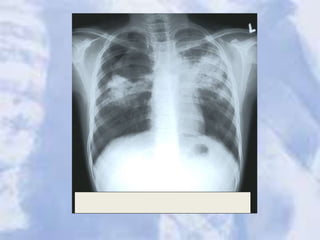

Right Middle and Left Upper Lobe Pneumonia

Right Middle andLeft Upper Lobe Pneumonia